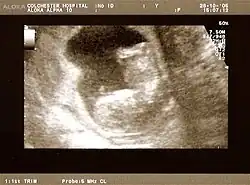

3D ultrasound of 75-millimetre (3.0 in) fetus (about 14 weeks gestational age) -

Obstetric ultrasonography is routinely used for dating the gestational age of a pregnancy from the size of the fetus, determine the number of fetuses and placentae, evaluate for an ectopic pregnancy and first trimester bleeding, the most accurate dating being in first trimester before the growth of the foetus has been significantly influenced by other factors.[22] Ultrasound is also used for detecting congenital anomalies (or other foetal anomalies) and determining the biophysical profiles (BPP), which are generally easier to detect in the second trimester when the foetal structures are larger and more developed.[23]

The safety of frequent ultrasound scanning has not been confirmed. Despite this, increasing numbers of women are choosing to have additional scans for no medical purpose, such as gender scans, 3D and 4D scans.[27] A normal gestation would reveal a gestational sac, yolk sac, and fetal pole.[28]

The gestational age can be assessed by evaluating the mean gestational sac diameter (MGD) before week 6, and the crown-rump length after week 6. Multiple gestation is evaluated by the number of placentae and amniotic sacs present.[29]